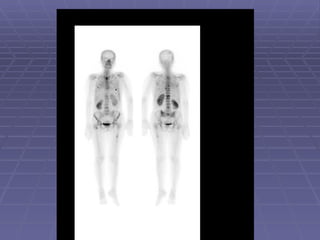

Stress Fractures It is often difficult to visualized on a plain radiograph. Fractures may be identified by bone scan as early as 24 hours after occurrence. 3-phase bone scan is usually done. There is hyperemia and osteoblastic process (three phases are positive).

• #33 57 year old man with painful left ankle. Plain films showed an area of sclerosis at the distal left tibia. Pertinent Findings: Blood flow images demonstrate an increase in activity in the distal left tibia. The bone scan shows increased activity along the anterior cortex and at the site of sclerosis. Diagnosis: Insufficiency fracture of the distal left tibia. Discussion : Stress fractures are either insufficiency or fatigue fractures. Insufficiency fractures occur in the setting of normal stress applied to abnormal bone. Abnormality of bone includes diminshed elasticity, deficient mineralization. Fatigue fractures result when abnormal stress is applied to normal bone.

• #34 Clinical History: Pain in the right foot for three weeks. Findings: Nuclear Medicine Bone Scan: A single focus of increased radiopharmaceutical activity is identified on all three phases within the distal right fourth metatarsal. Diagnosis: Stress fracture. Discussion: A stress fracture is the result of repetitive, prolonged muscular action on a bone that has not accommodated itself to that action. In most instances, persons who have stress fractures are engaged in vigorous activity to which they have not yet become conditioned. Under normal circumstances, the muscle tone takes up at a faster rate than bones which result in a mechanical imbalance. Stress fractures are divided into two categories, fatigue fractures and insufficiency fractures. A fatigue fracture is caused by the application of abnormal stress or torque on a bone that has normal elastic resistance. On the other hand, an insufficiency fracture occurs when normal muscular activity stresses a bone that is deficient in mineral or elastic resistance. The term pathologic fracture should be reserved for fractures that occur in bone already weakened by neoplasm or infection. The stress placed on bone causes resorption and microfractures. If the patient rests and the stress decreases then repair may continue with resultant relief of pain. However, if the repair process can no longer keep up with the resorptive process, then cortical disruption and a radiographically visible fracture may ensue. Findings develop earlier on bone scan and MRI than on plain film roentgenograms. A hot spot on all three phases of a bone scan is a bone that has received repetitive trauma is indicative of a stress fracture. Type sites for athletic stress fractures include:Tibial and fibular shaft ;Medial aspect of the femoral neck ;Inferior pubic ramus ;Metatarsals and os calcis ;Navicular and tarsal sesamoids